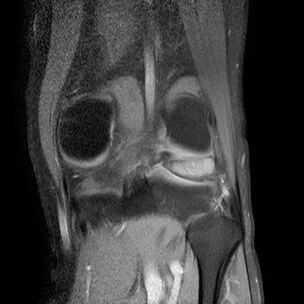

半月板斜行撕裂

最常见类型:斜行撕裂表现为:在矢状面上见III级高信号到达半月板关节面的上缘或下缘